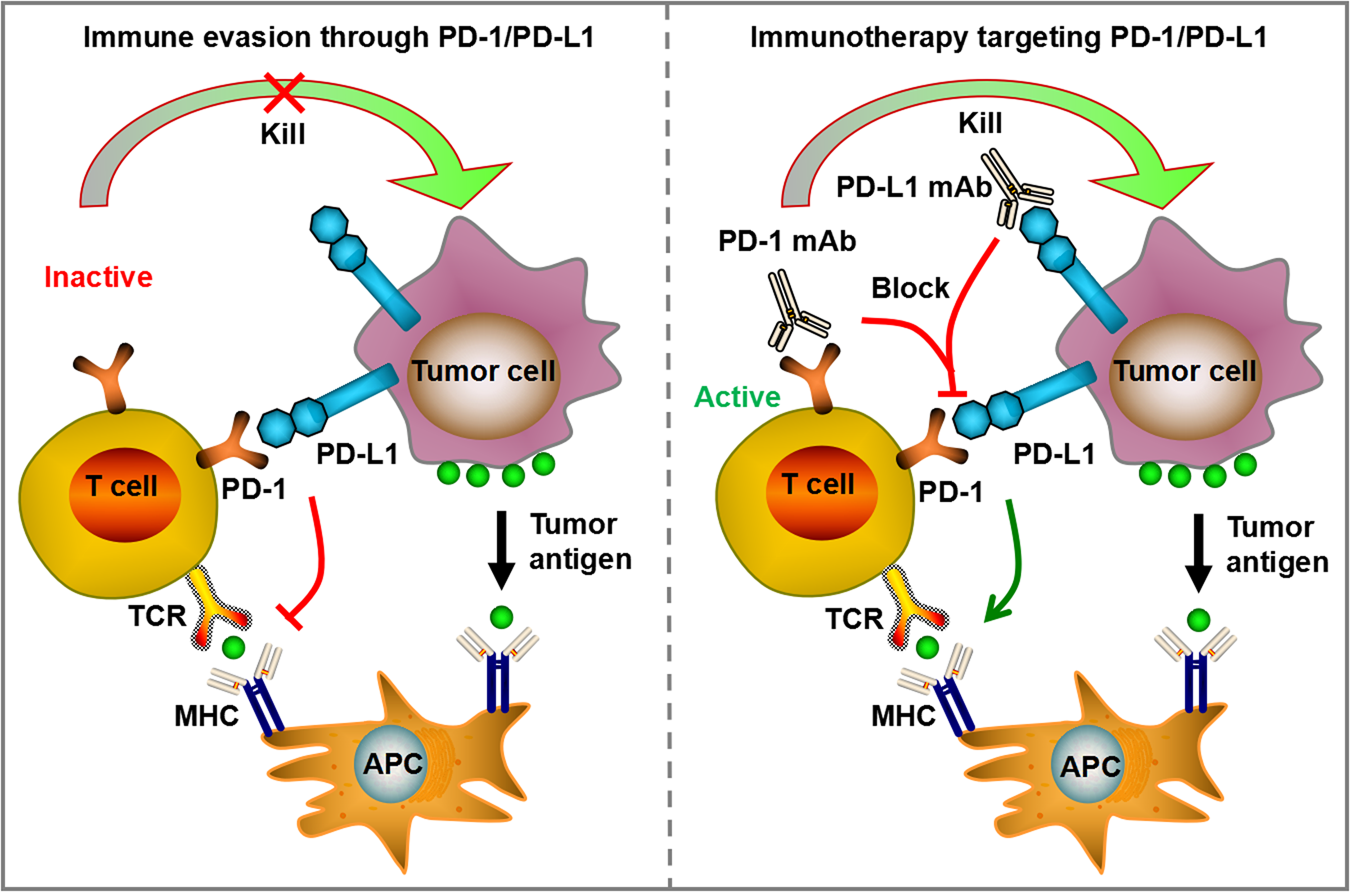

Immunotherapy and Adrenal Insufficiency: When Treatment Saves You… But Changes You

Why does the NHS not fund further melanoma treatment if patient can not tolerate 2 years of Nivo?

What are each of the doses of IpiNivo doing biologically?

Why do Oncologists only use 4 doses of IpiNivo in the treatment of Metastatic Melanoma?